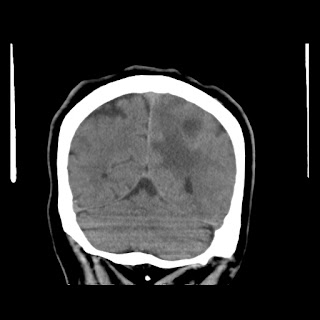

Caso neurorradiología

Paciente de 60 años con cuadro de 1 semana de evolución consistente en tropiezos frecuentes y alteración en la movilidad del miembro

inferior derecho. No refiere

cefalea u otros síntomas asociados, no pérdida de peso, no náuseas o emesis, no

sudoración nocturna. Antecedentes de hipertensión arterial y diabetes.

Escanografía